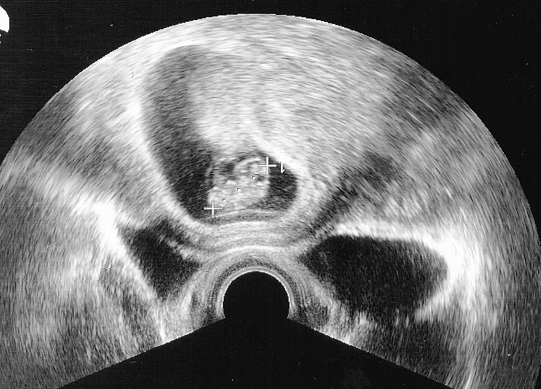

Rendez vous à l’hopital, et nous sommes chanceux, cette fois ci il y a très peu d’attente. Nous faisons donc une rapide écho et le medecin nous dit : « non vraiment, désolé, mais je ne vois rien du tout »

Demie-deception de ma part, mais je m’y attendais un peu. Je me dis intérieurement « rendez-vous le mois prochain ! ». Le medecin éteint sa machine, mais la rallume et refait un essai, et la, il nous annonce : « Ha, vous allez devoir vous mettre à jouer à la poupée on dirait »

Donc apparement, ce serait une fille. N’ayant aucune préférence, j’ai bien sur été fou de joie, tout comme ma femme :) On reste cependant un peu prudent car il arrive que les medecins se trompent. Il suffit de regarder l’écho (photo suivante) pour comprendre, ou plutôt ne pas comprendre comment il en a déduit ca :x

echo

La, sous la flèche, ce n’est pas un zizi, donc c’est une fille (cf le medecin)